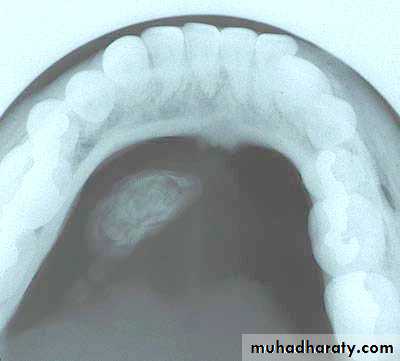

Sialolithiasis (calculi) cont’d

Submandibular Gland - Sialolithiasis

Diagnosis

Pain and sudden enlargement of gland while eating

Palpation of stone in the submandibular duct

Occlusal radiograph (80%)

Sialogram